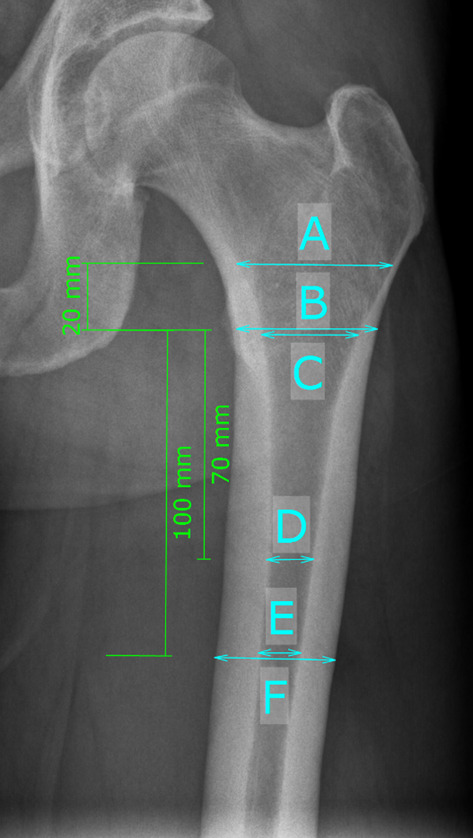

Methods: A retrospective, single-center, multi-surgeon, comparative propensity-score matched study of a cohort of 1826 short stem THAs was conducted. A total of 39 PFFs within the first 90 days after surgery was matched on a 2:1 ratio to non-fracture patients. The morphology of the proximal femur was analyzed with canal flare index (CFI), canal-calcar ratio (CCR), canal-bone ratio (CBR), morphological cortical index (MCI), and femoral cortical index (CI). The pelvic morphology was analyzed with ilium-ischial ratio (IR), distance anterior superior iliac spine to the tip of the greater trochanter (AGT). Both groups were analyzed regarding several parameters for femoral and pelvic morphology in non-parametric testing and univariate regression analysis.